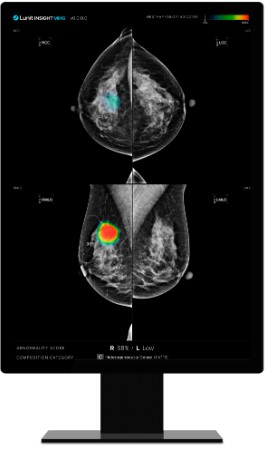

의료 인공지능(AI) 기업 루닛(대표 서범석)은 유방촬영술 AI 영상분석 솔루션 '루닛 인사이트 MMG'의 유방암 조기 발견 및 의료진 업무 경감 효과를 입증한 유럽 연구 2건이 세계적 권위 의학 저널에 게재됐다고 23일 밝혔다.

AI는 각 유방에 0부터 100까지의 점수를 부여하는데, 점수가 높을수록 유방암 가능성이 높음을 의미한다.

연구 결과, 나중에 암이 발견된 유방과 그렇지 않은 반대쪽 유방 사이 평균 AI 점수 차이가 시간이 지남에 따라 증가했다. 이 차이는 첫 번째 검진에서 평균 21.3점, 두 번째 검진에서 30.7점, 세 번째 검진에서 79.0점으로 크게 증가했다. 반면, 유방암이 발생하지 않은 여성들 경우 양쪽 유방 사이 점수 차이가 모든 검진에서 10점 이하로 낮게 유지됐다.

또한 연구팀은 AI 점수 91.3 이상인 상위 1%를 '고위험군'으로 분류했으며, 발견된 암환자 중 4.5%는 4~6년 전, 8.6%는 2~4년 전, 52.9%는 2년 전 양성 가능성을 보이는 AI 점수(10점 이상)를 확인했다.